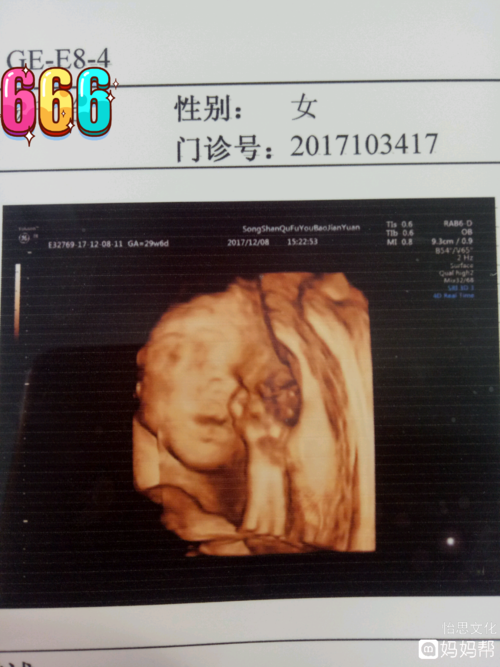

女宝四维图片

生女儿的四维彩超图片

确认女宝四维图

已生了女宝的四维单子

女宝特征的四维图

已生女宝的四维图

最明显的女宝四维图